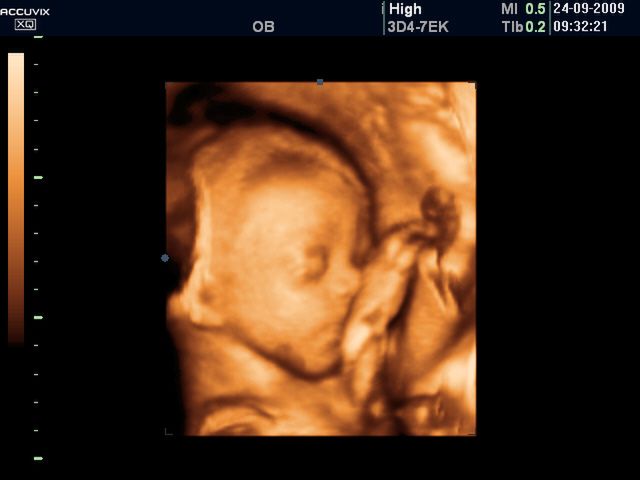

/ 5Płód w 26 tygodniu ciąży - ssanie palca

Dziecko często ssie swój palec